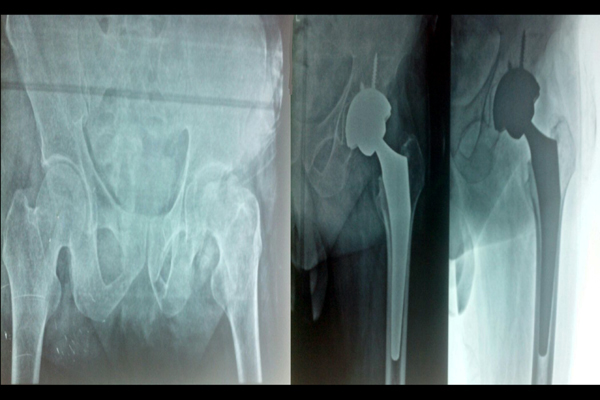

Reiterate the benefits of choosing the hospital for Orthopaedic, Physiotherapist, and Pathology care. Invite visitors to take the first step towards a pain-free life by clicking the call-to-action button.